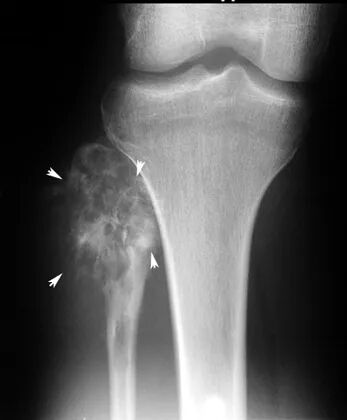

在X光片中,骨肉瘤有阳光四射一样的形态(sunburst)。梅奥医学中心的肿瘤血液学家 Carola Arndt 介绍,骨肉瘤是最恶性的骨癌之一。

骨肉瘤有阳光四射一样的形态

图片来源:芝加哥大学医学院

和身体其他部位的骨头相比,骨肉瘤喜欢长在长骨的生长板(或称骺板)上面。患者的肢端常常感觉疼痛,夜晚更痛,并且会长出一个鼓包。